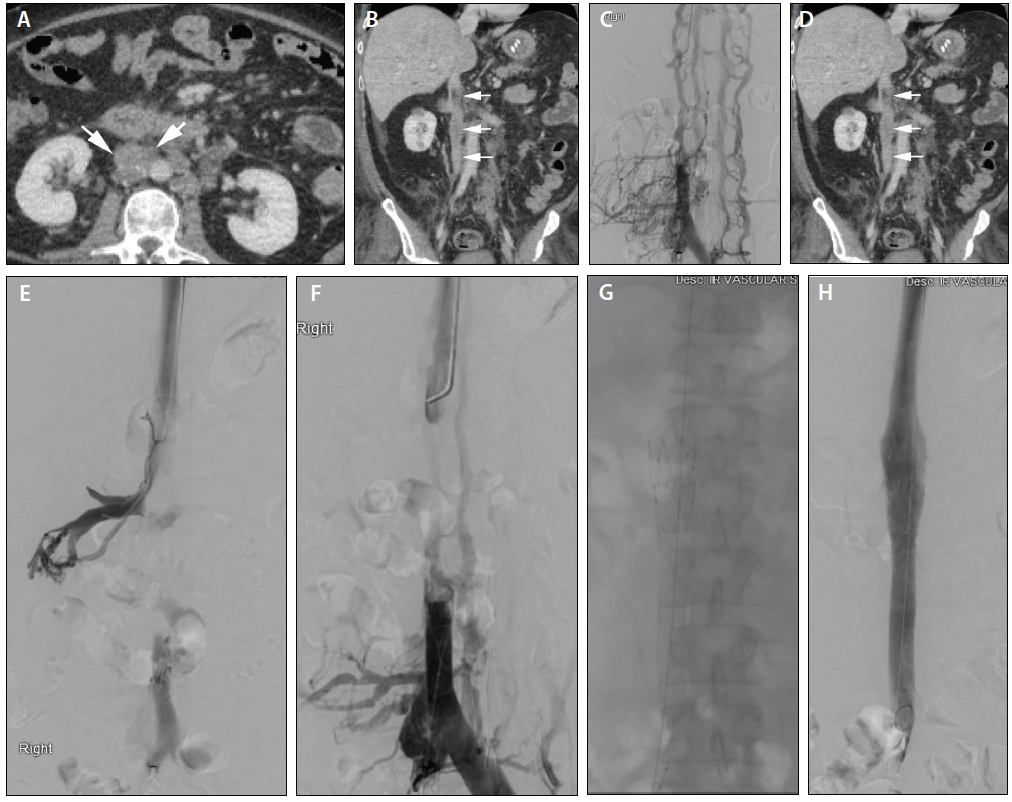

• Figure S3. Splanchnic Vein Thrombosis In Patient 4. Venous Phase CT ...